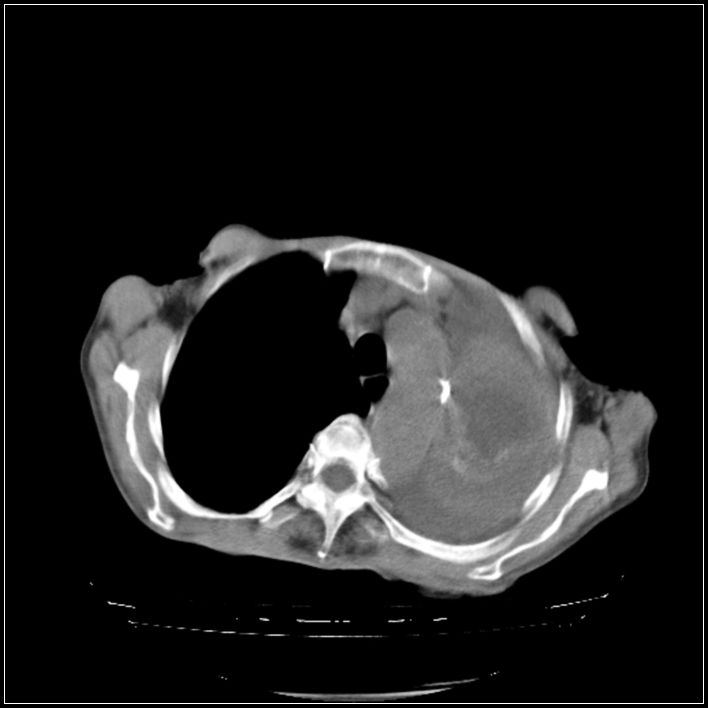

以下是引用影象小辈在2008-5-31 16:25:00的发言:[br]左侧胸腔团状不规则致密影,界欠规整,密度不均匀,其内可见更低密度影及高密度影,并可见包裹性胸腔积液 考虑为1.畸胎瘤 2.肺癌